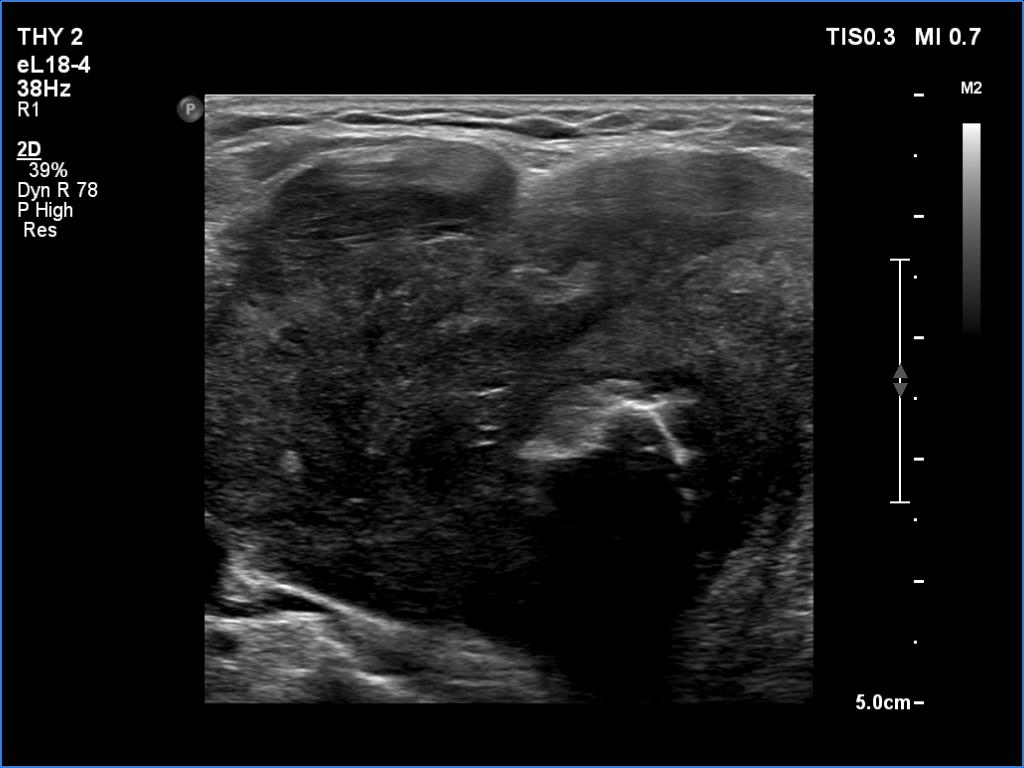

Ultrasonography. There was an irregular, large hypoechoic mass in the right lobe. The nodule has irregular, lobulated margins and was hard on elastography. A much smaller, similar nodule was in the lower-medial part of the left lobe.